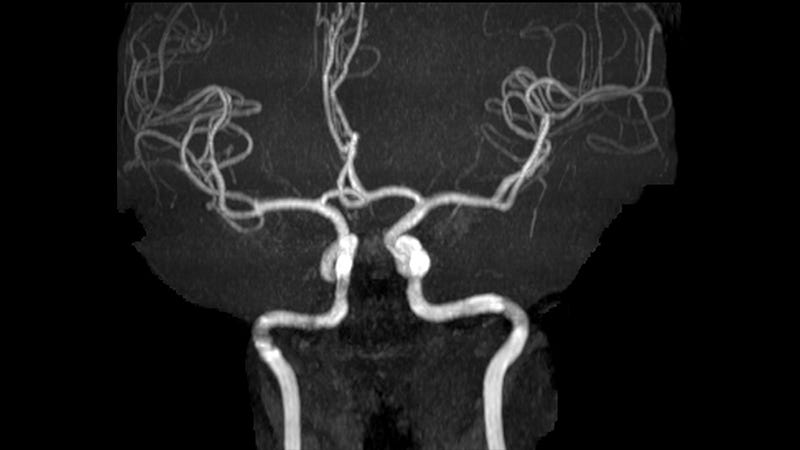

Angiografia cerebral mostrando um aneurisma sacular (seta ...

Angiografia cerebral mostrando um aneurisma sacular (seta ... from www.researchgate.net

Angio-RM cerebral

Angio-RM cerebral from www.radiologiadealbufeira.pt